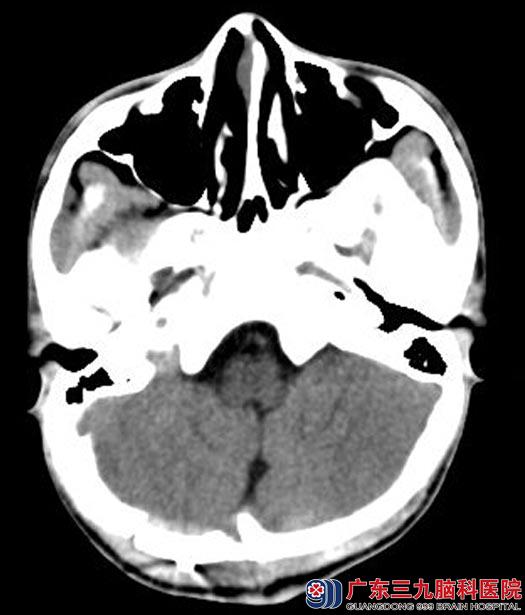

呕吐数次,复查头颅CT提示双侧枕部硬膜外血肿增加,急诊在全麻下行双侧枕部硬膜外血肿清除术,术中见硬膜外暗红色血性液体并暗黑色血凝块,予以清除,量约40ml,硬膜多处渗血;彻底止血顺利,术后阳阳恢复得很快,两周后即康复出院。

手术后